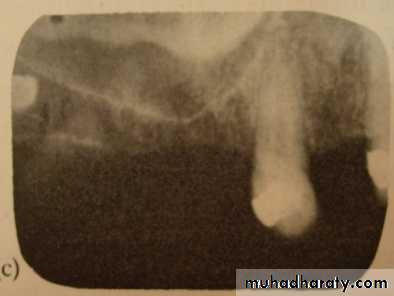

• Radiographs

• A complete series of periapical and bitewing radiographs is essential for complete examination.• Panoramic radiographs are ideal for screening for pathologic conditions.

• Excellent periapical radiographs are essential for determining the crown/ root ratio of the remaining teeth, the status of periodontal ligament space, and lamina dura, quality of ridge in the edentulous areas.